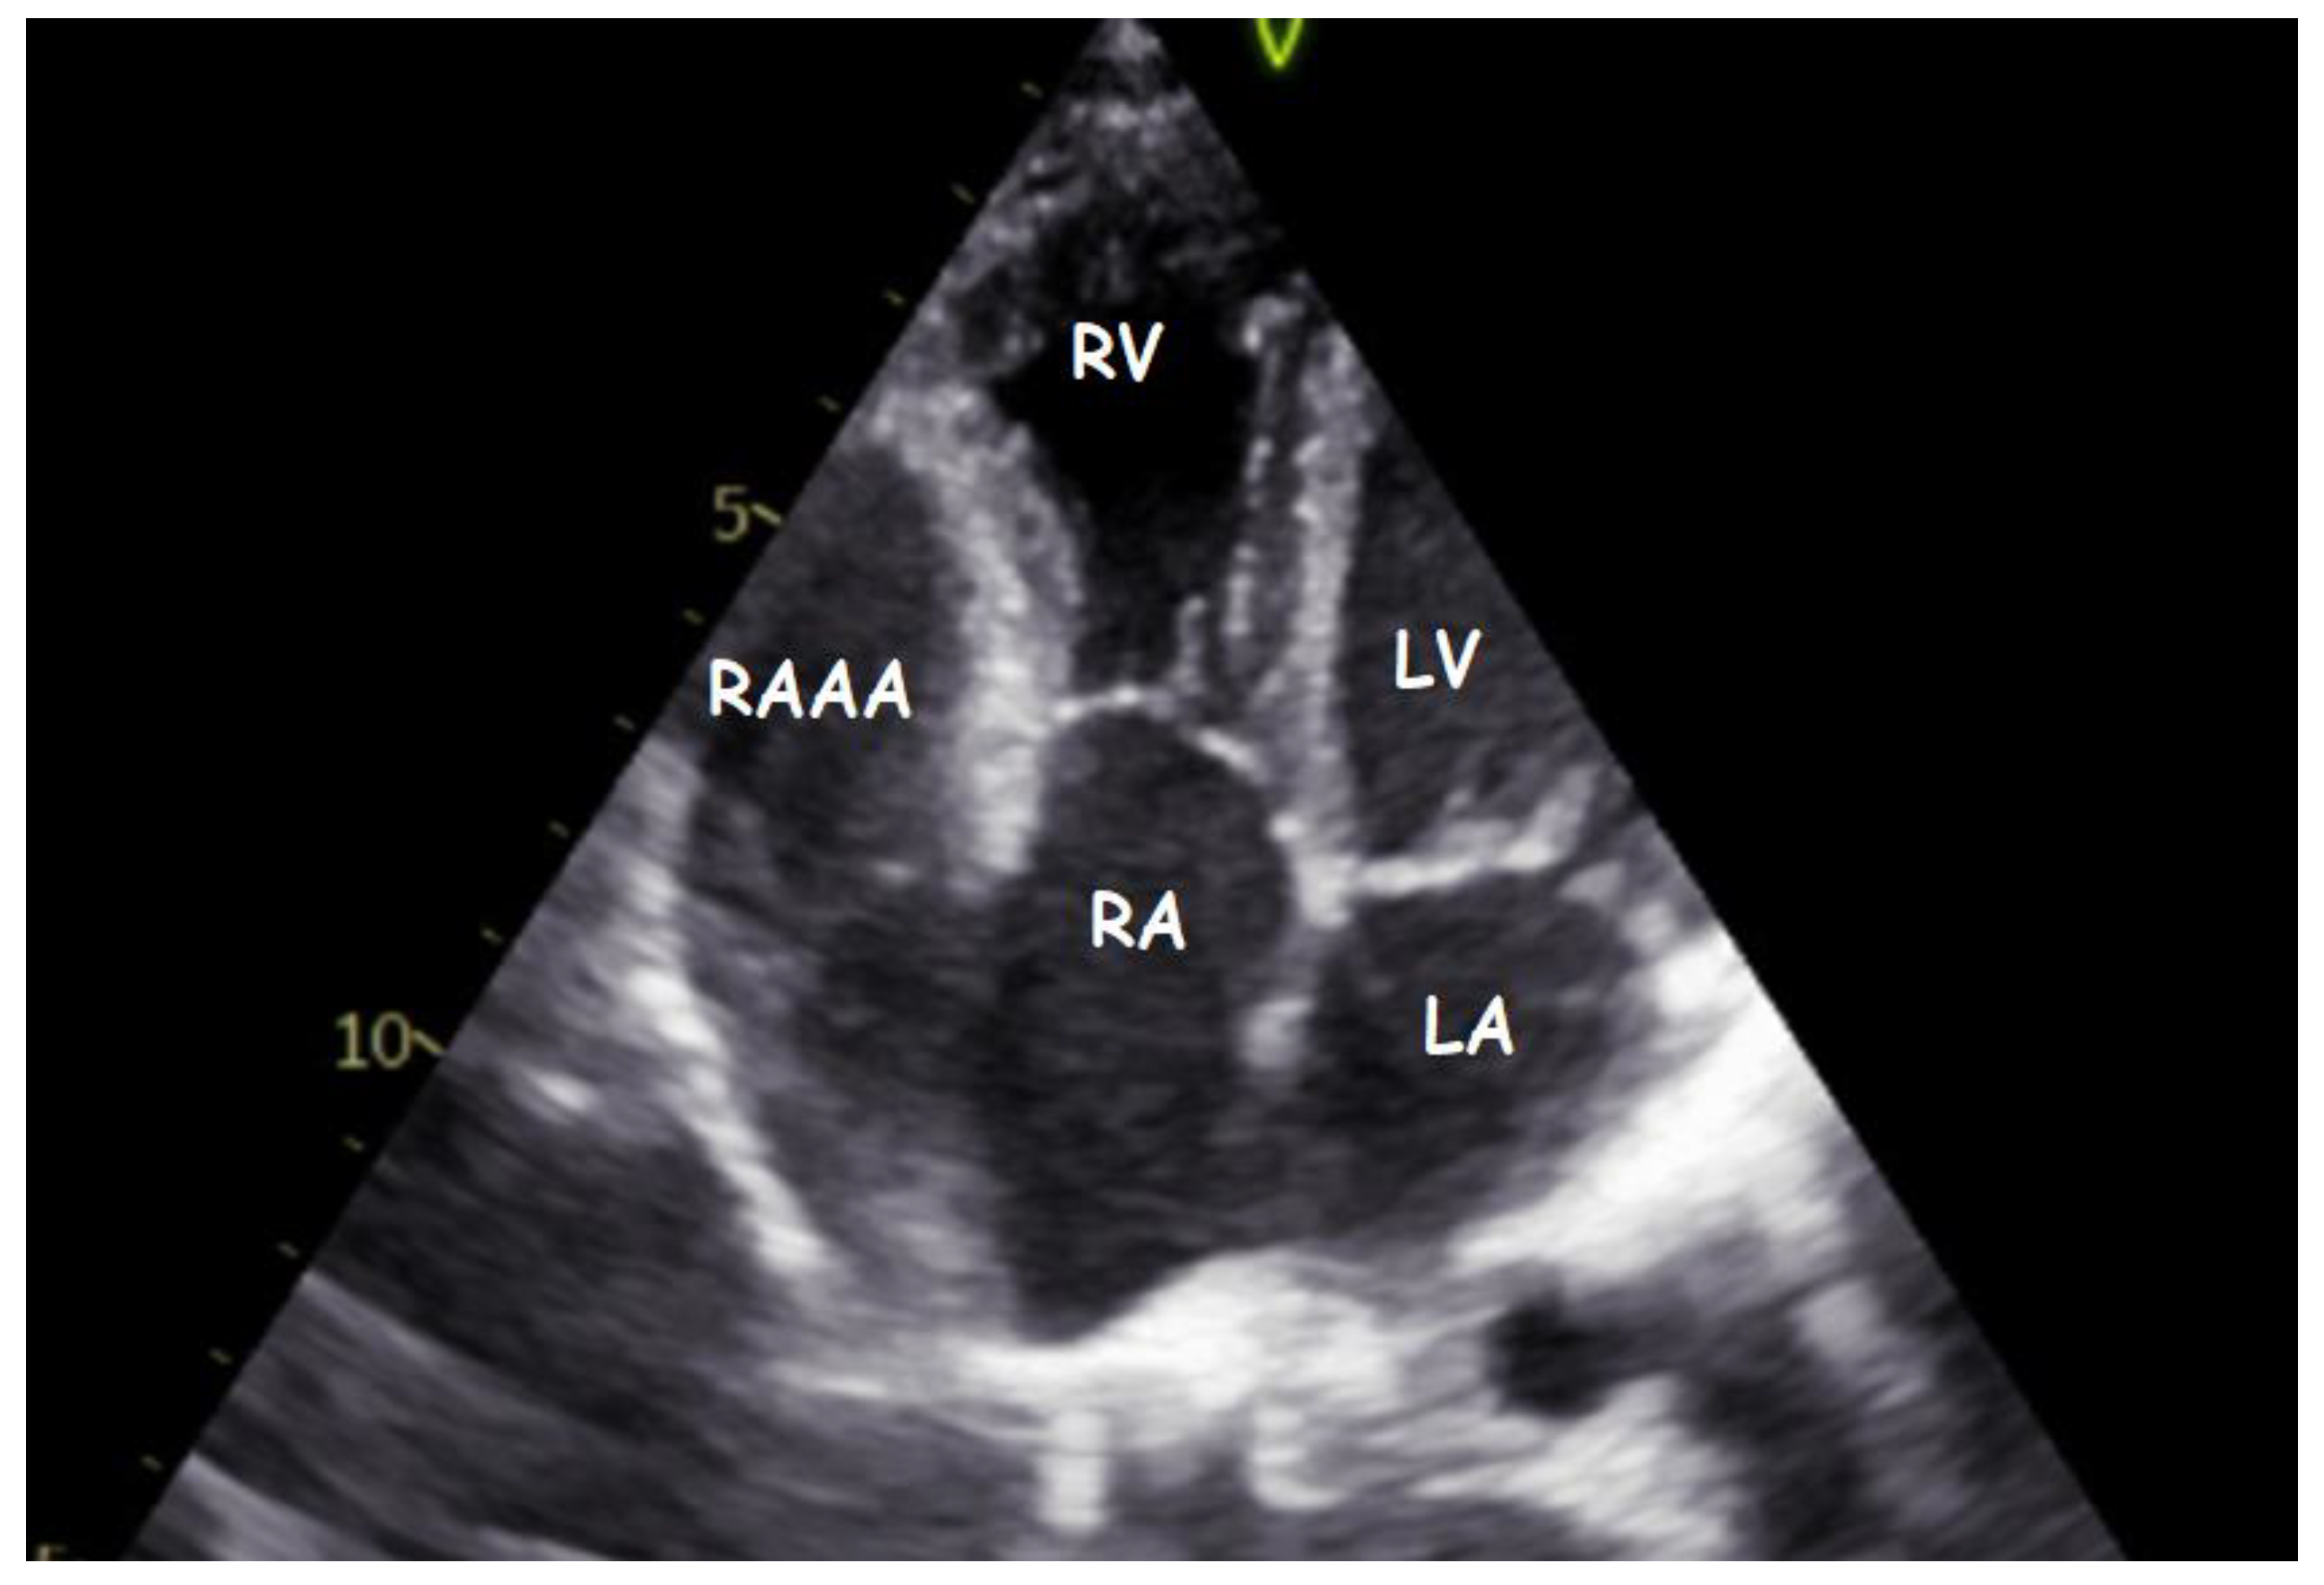

A Gigantic Congenital Right Atrial Appendage Aneurysm in an Infant: Ten-Year Follow-Up

1. Clinical Presentation